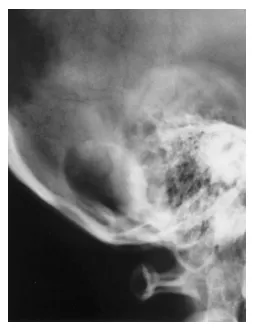

患者为55岁女性,主诉头痛和左眼疼痛,2005年11月就诊于当地医院。因诊断为左小脑肿瘤转至上级医院接受手术治疗。体格检查及神经系统检查未见异常。头颅X线片显示枕骨存在溶骨性病变(图1)。